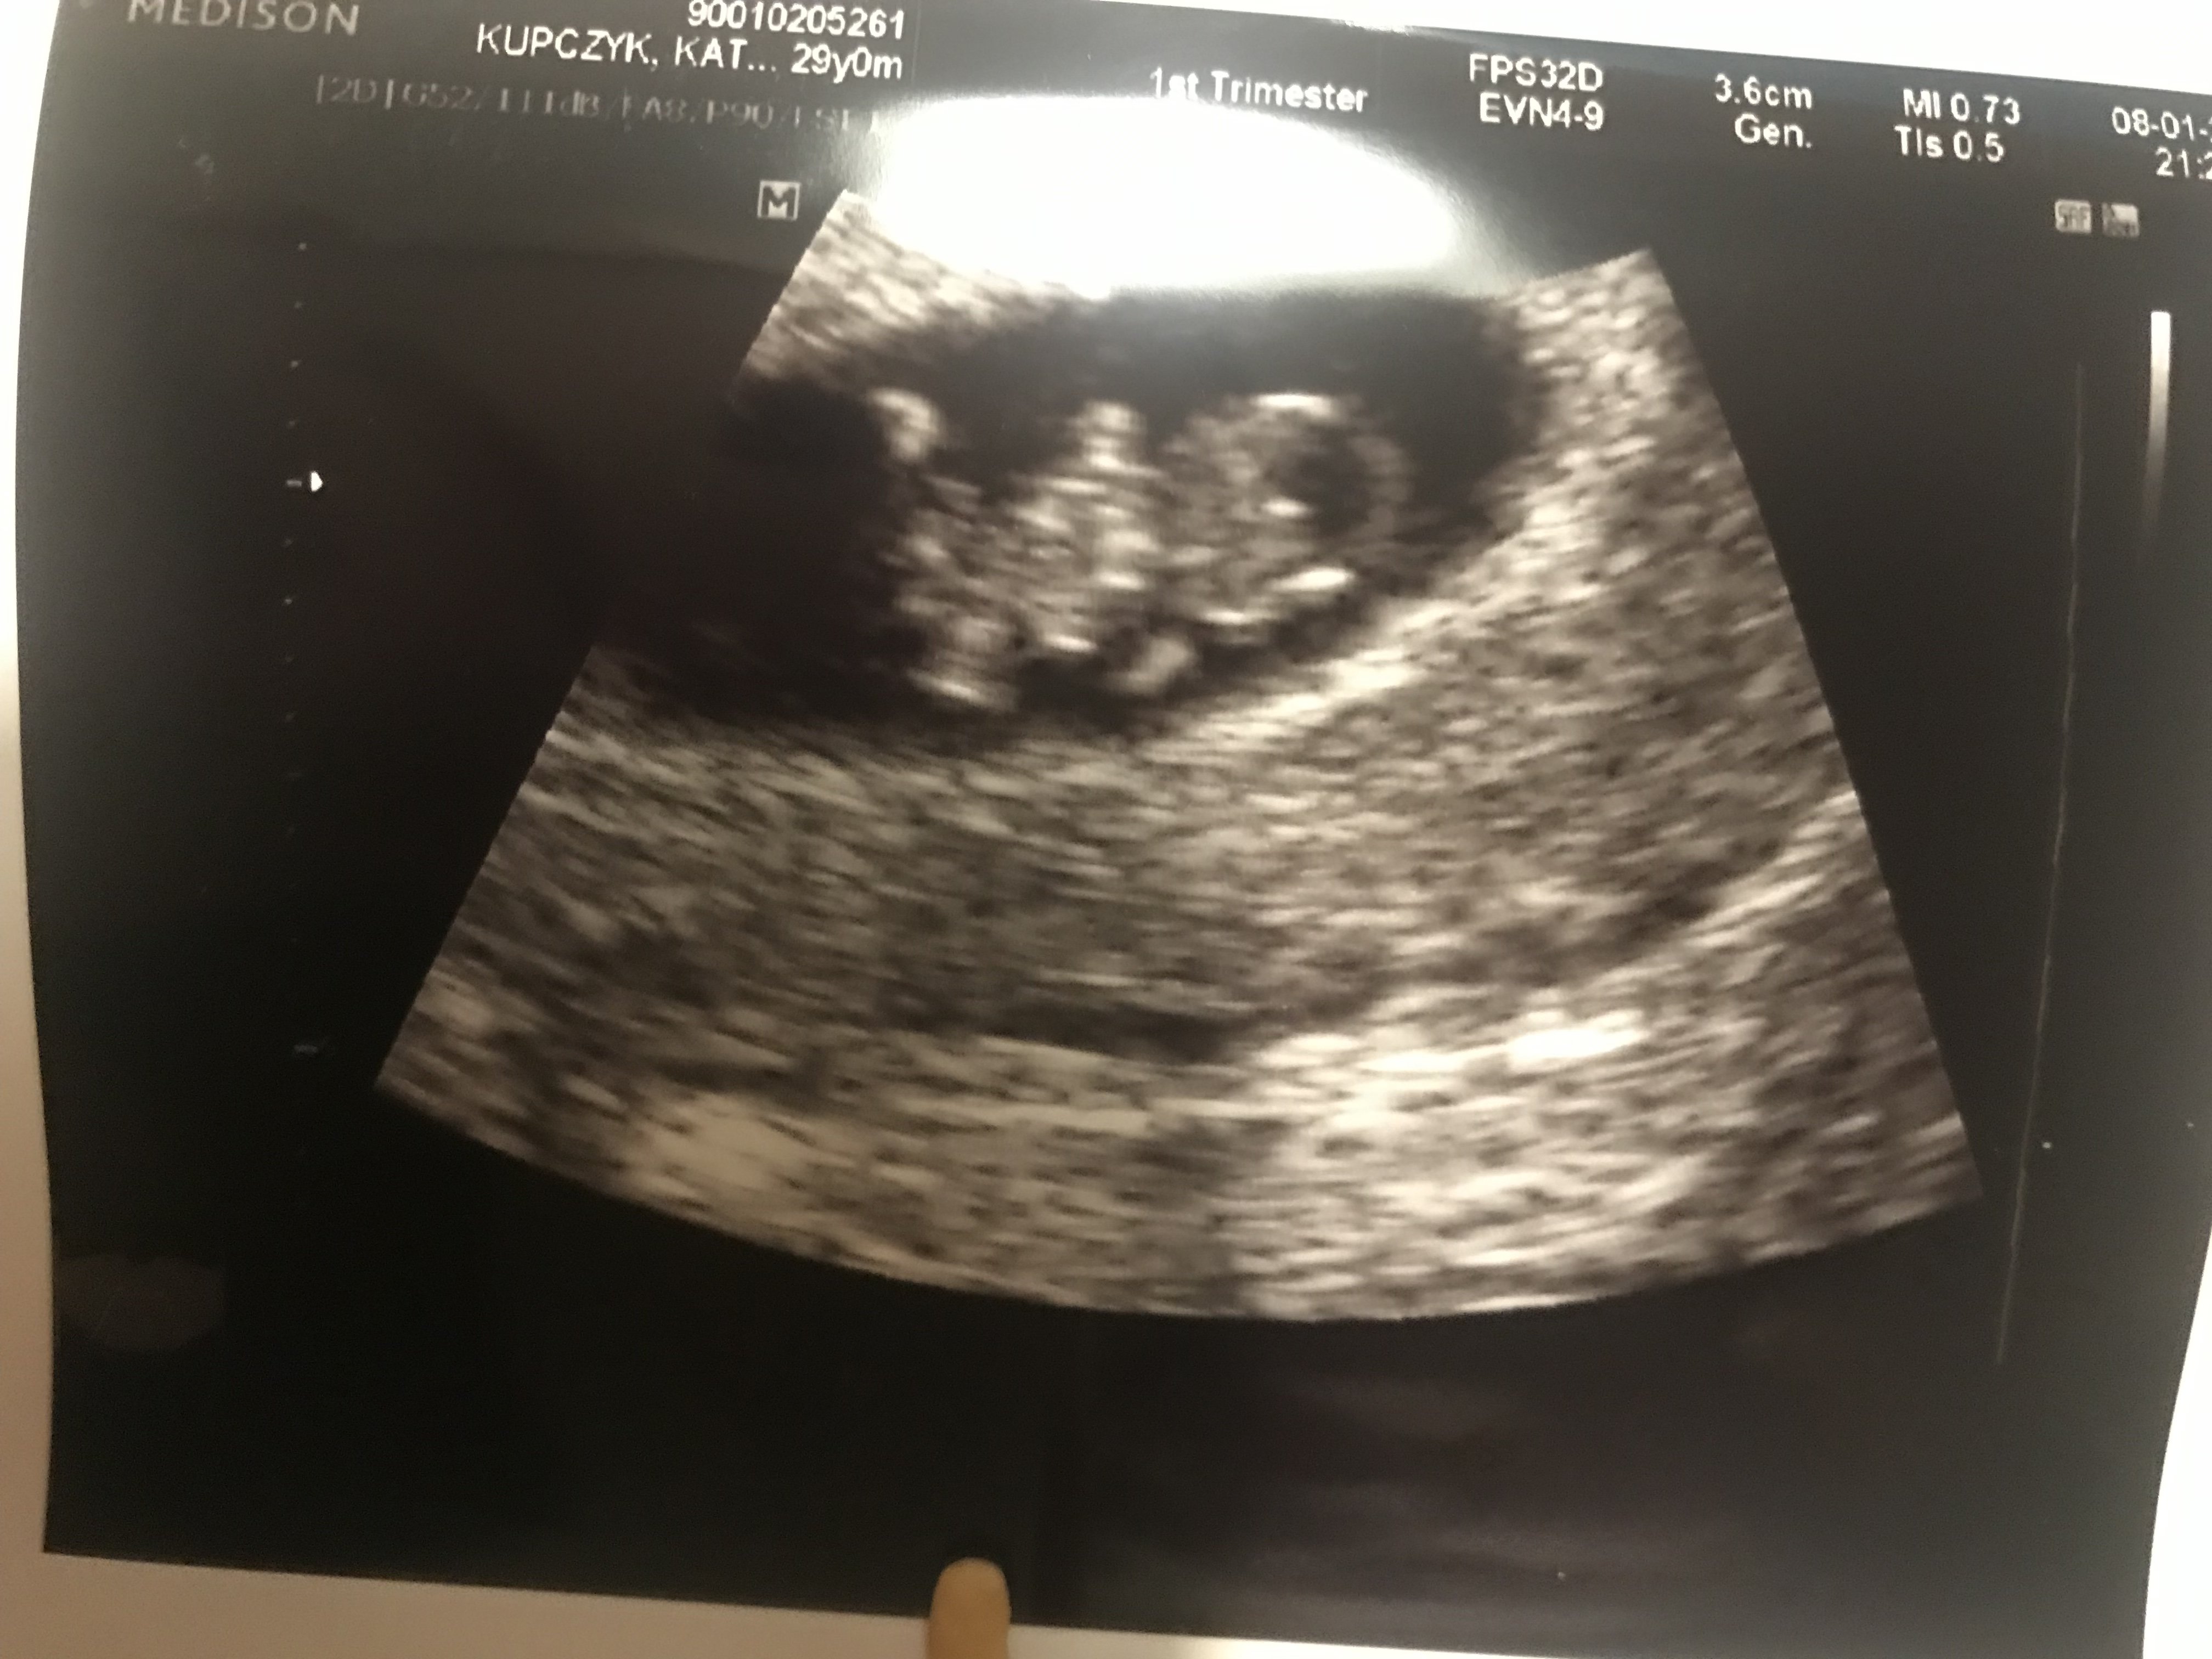

Hej dziewczyny. Ja chwale się zdjęciem Robaka. Robak zdrowy, 17mm, młodszy o tydzień niż wynika z om czyli 8+2 dzisiaj. Termin niby 14.08, tak nadal kazał liczyc według miesiaczki. Wiec proszę o dopisanie do listy

słodziak :) jeju jak tak pomyślę 17 mm a mój już 34 mm to dwa tygodnie temu tyle miał, rośnie jak na drożdżach :)